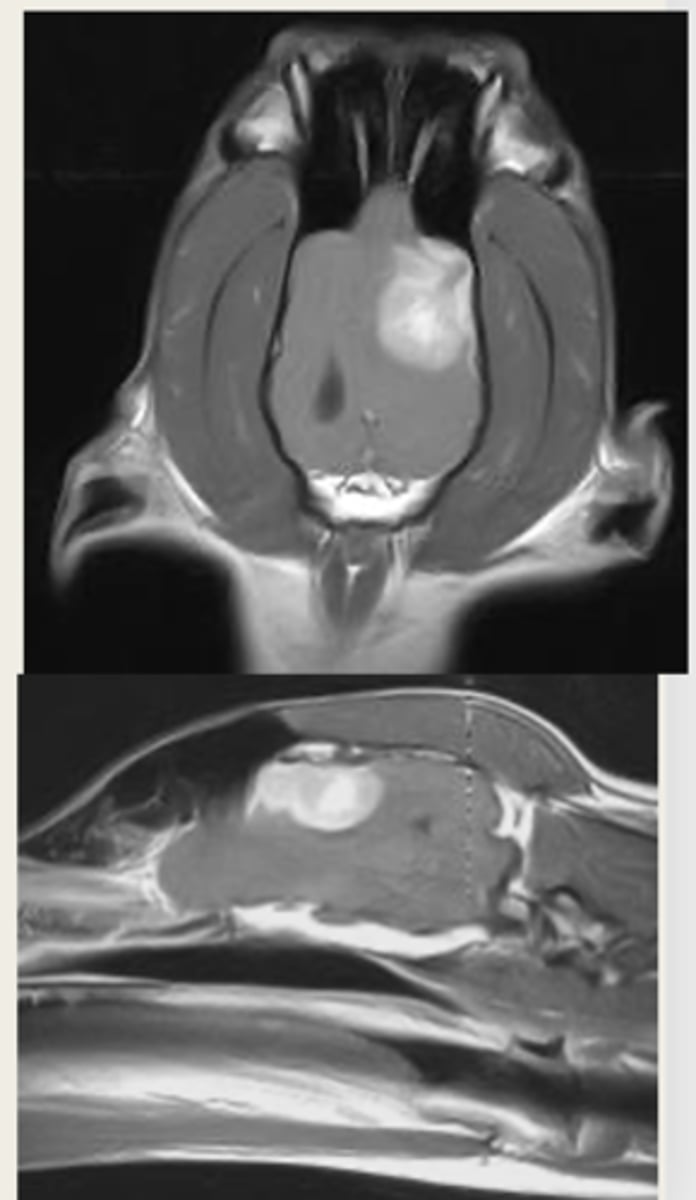

left- T1 weighted

right- T2 weighted

which MRI image is T1 or T2 weighted?